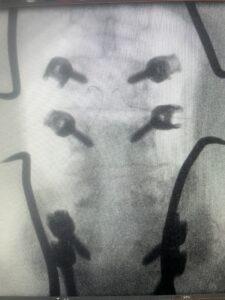

This 61-year-old female with a history of severe osteoporosis and a prior history of a laminectomy from l2-S1 with an L5-S1 instrumented fusion, presents with progressive low back pain and right lower extremity radiculopathy. MRI revealed a grade 1 L2-3 spondylolisthesis with severe stenosis mainly from severe right L2-3 facet joint hypertrophy which was compressing the right L3 descending nerve root. (Fig. 1). She had failed conservative management consisting of physical therapy and pain management with epidurals. She underwent an L1-3 revision laminectomy where we had to dissect a plane underneath the inferior aspect of the L2 lamina. We performed an instrumented fusion at L2-3 with special hydroxyapatite-coated screws to improve fixation to surrounding bone given here severe osteoporosis (Fig. 2) This worked out well and the patient had an uneventful recovery with relief of her leg pain.

Fig: 2a: AP and lateral intraoperative fluoroscopic images demonstrating good placement of L2-3 pedicle screws